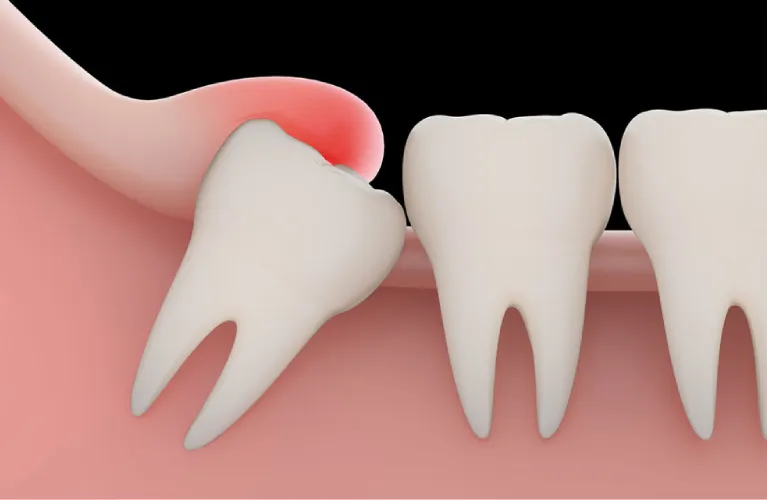

Periodontal disease

Advanced gum disease can cause the supporting tissues and bone around a tooth to deteriorate, making extraction the only option.